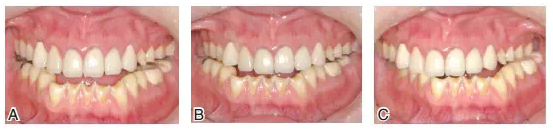

圖8患者J初診時的上頜咬合面可見舌尖明顯磨耗,橫牙合曲線呈上凸的倒曲線

圖14根據(jù)診斷蠟型制作暫時冠戴入上頜。A.上頜后牙診斷蠟型;B.根據(jù)診斷蠟型翻制的暫時冠;C.暫時冠戴入口內